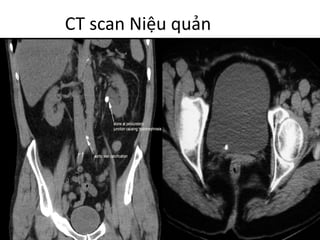

CT	scan	Niệu quản

Giải phẫu:

- Dài 25-30 cm và có ba

phần:

Niệu quản bụng: từ thận

đến khung xương chậu

Niệu quản Chậu: từ

khung xương chậu đến

bàng quang

Niệu quản nội màng hoặc

nội mạc: trong thành bàng

quang

- Đường kính bình thường

</=3mm [1]

[1]	Normal	Ureter	Size	on	Unenhanced	Helical	CT

Natalie	Zelenko1, Deidre	Coll2, Arthur	T.

Rosenfeld3 and Robert	C.	Smith4

• Khảo sát được toàn bộ đường đi niệu quản,

cũng như toàn bộ hệ niệu

• Khảo sát các tổn thương liên quan xung

quanh.

• Quan sát rõ nhất thành,	lòng niệu quản trên

thì thận đồ,	delay.

Chẩn đoán:

- Nhiễm trùng

- Tắc nghẽn (phân độ,	tìm nguyên nhân:	ung thư,

sỏi cản quang,	xơ dính)

- Chấn thương:	đứt,	rách niệu quản (thoát nước

tiểu)

- Dị tật bẩm sinh:	Các bất thường vị trí xuất phát,

số lượng,	đường đi,	vị trí đổ vào bang	quang

(niệu quản đôi,	lạc chỗ,	bất sản,	túi thừa…)

CT	scan	Niệu

quản

• Không thuốc tương phản.

- Chẩn đoán mức độ ứ	nước thận

(4	độ)

- Chẩn đoán nguyên nhân gây tắc

ngẽn:

Sỏi niệu quản đoạn chậu.

Đo chính xác kích thước 3	chiều,	vị

trí

sỏi kẹt ->	định hướng điều trị.

- Dựng hình tái tạo theo đường

cong (CPR)

giúp các PTV	tiếp cận dễ đàng hơn.